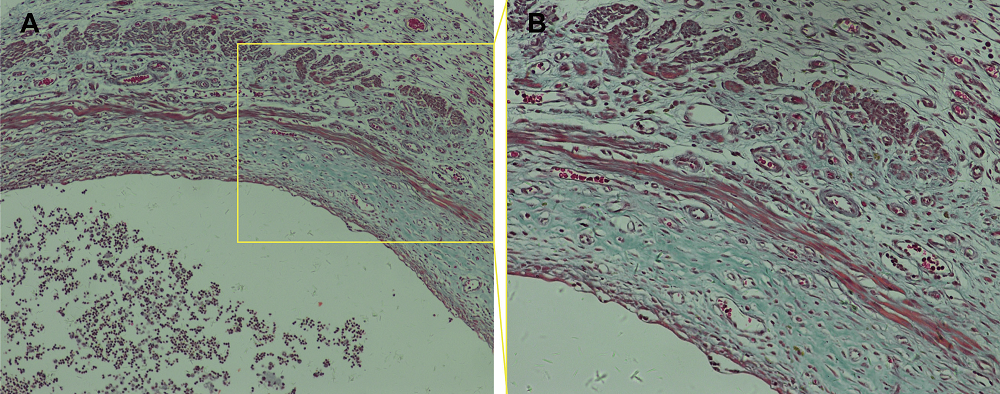

After 2 weeks, three rats were randomly selected and administered a lethal dose of 50% chloral hydrate. The abdominal cavity was dissected and endometriotic lesions were clearly visible on both sides of the abdominal cavity in each of the three rats. The tissue from these rats was fixed and embedded in paraffin, serial sections cut, and Masson’s staining performed on sections to examine endometriotic lesion formation and fibrosis (Figure 2).

Figure 2.

Figure 2.— Representative photomicrograph of the cystic walls from rat endometriotic lesions after Masson’s staining (A: 100 ×; B: 200 ×).